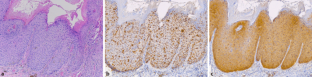

Abb. 1

23. Kreuter A, Siorokos C, Oellig F et al (2016) High-grade Dysplasia in anogenital warts of HIV-positive men. JAMA Dermatol 152:1225–1230